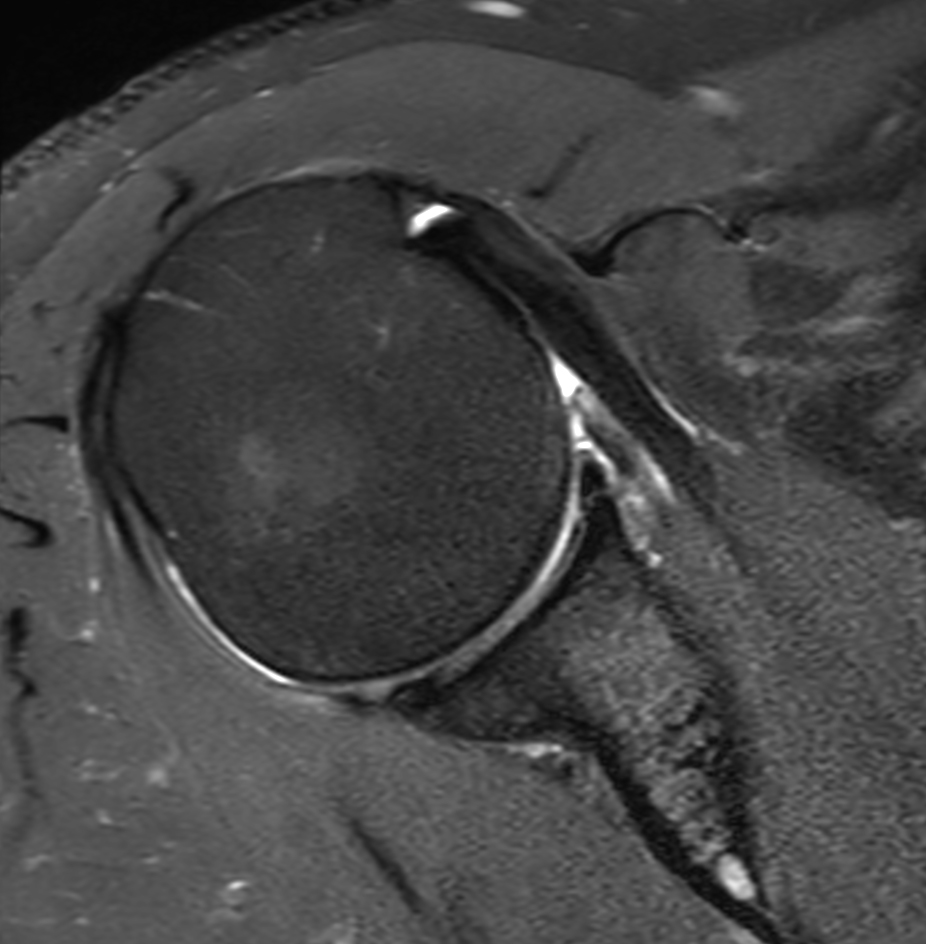

High resolution imaging with the dS 16ch Shoulder coil and Compressed SENSE